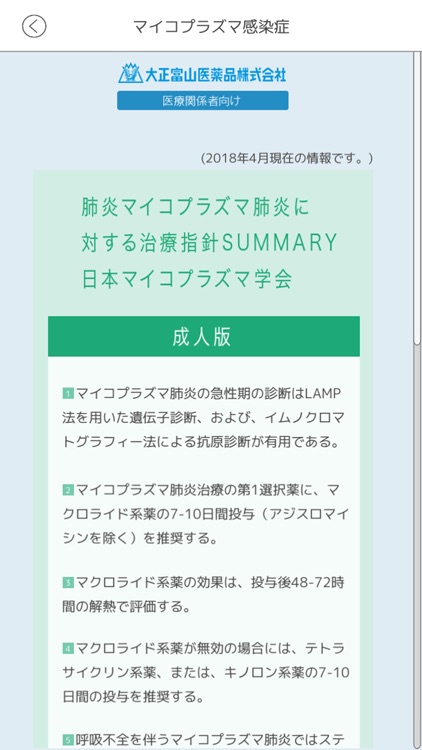

②各疾患の診断・治療において参考となる情報をすぐに参照できます。(画面2)